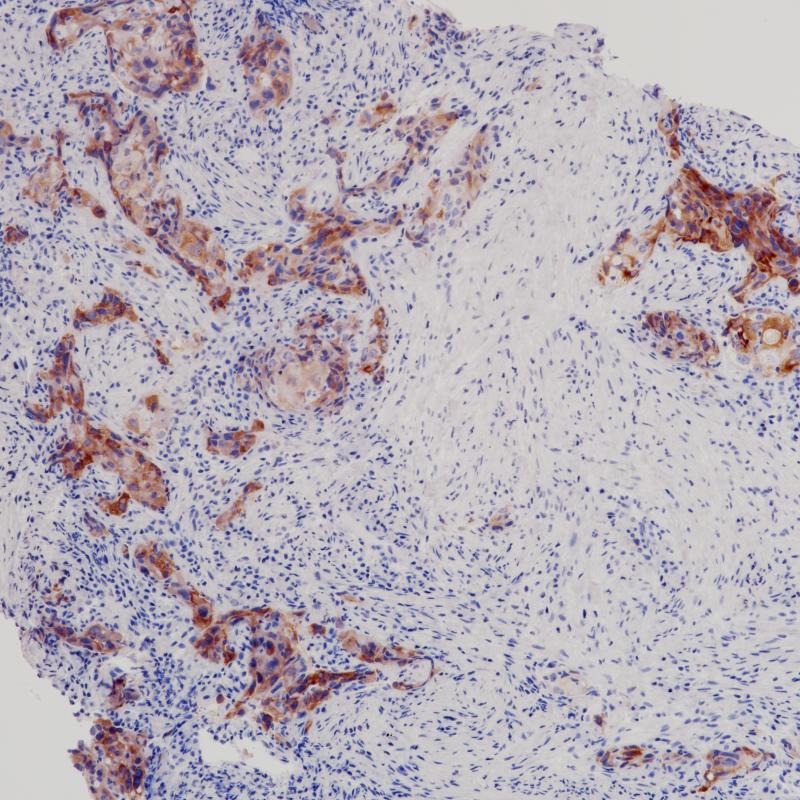

肺癌ROS1(BP6215)染色

ROS1

重组兔单克隆抗体

ROS1是胰岛素受体家族的一种孤儿受体酪氨酸激酶,最初被鉴定为UR2肉瘤病毒V-ros的同源物。ROS1由一个大的细胞外结构域组成,该结构域由6个纤维连接蛋白重复序列、一个跨膜结构域和一个细胞内激酶结构域组成。ROS1已被证实在附睾上皮分化中发挥重要作用。ROS1的第一个致瘤融合图-ROS1最初是在胶质母细胞瘤的研究中发现的。

阳性对照

肺癌

亚细胞定位

细胞质